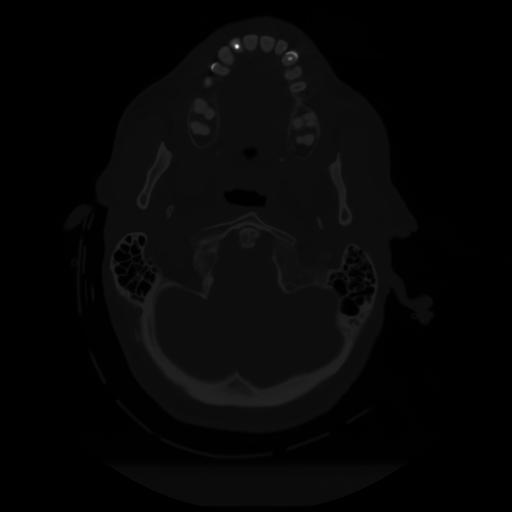

10 P.BLANDAS,,Axial,2.0,P.BLANDAS,,